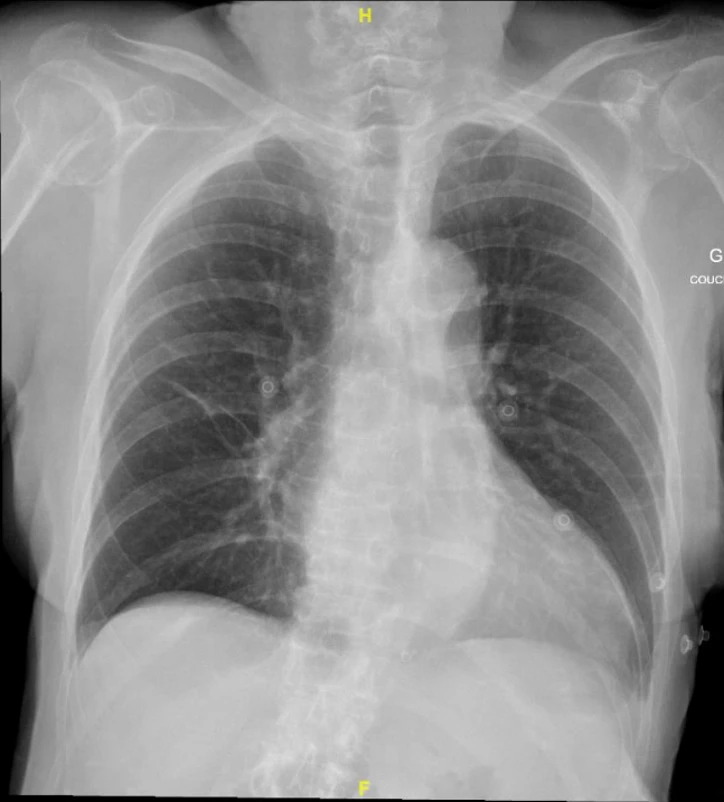

Madame X est une patiente de 89 ans, connue pour une démence, qui se présente aux urgences avec une baisse de l’état général depuis une semaine. Elle décrit une dyspnée d’effort et une légère toux. Le reste de l’anamnèse par système est non contributive, elle ne rapporte notamment pas de chute récente. L’examen clinique n’est pas relevant hormis une désaturation à 91% à l’air ambiant. Le bilan biologique révèle un syndrome inflammatoire, une absence de cinétique des troponines, des D‑dimères dans la norme pour l’âge et un NT-pro-BNP dans la norme. L’ECG ne montre pas de modifications. La radiographie (Rx) du thorax ne révèle pas de signe de surcharge ni d’infiltrat mais elle révèle autre chose : une fracture multi-fragmentaire sous capitale de la tête humérale à droite.

Peu importe finalement l’analyse choisie pour une radiographie du thorax, ce qui est indispensable, c’est que l’observation soit systématique. La description de la Rx dans son ensemble est fondamentale pour la prise en charge d’un·e patient·e.

Proposition de check list :

• Bon·ne patient·e, bonne image

• Qualité du cliché (Symétrie, pénétrance, centrage, inspiration, Debout/​couché)​

• Analyse de la Rx sous le format ABCDEF :

◦ A : Airways (Voies aériennes)

◦ B : Bones (Os)

◦ C : Cardiomediastinal silhouette

◦ D : Diaphragm

◦ E : Extended Lungs/​Everything else (Tout le reste)

◦ F : Foreign bodies (Corps étranger)